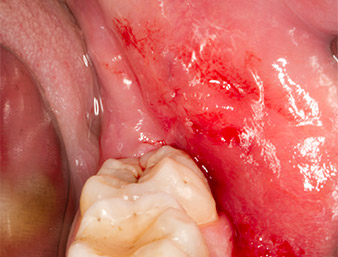

After block and local anaesthesia, the operating site was opened up and the soft tissue exposed for buccal retromolar access (Fig. 3).

sulcular incision

Fig. 3: The sulcular incision begins in mid-tooth 36 (LL6), with distal extension on the ascending ramus.

The tissue above the root remnant was not completely ossified and consisted for the most part of granulation tissue modified by inflammation (Fig. 4).

Granulation tissue

Fig. 4: Two Langenbeck retractors and a raspatorium expose the operating area. Granulation tissue of the incompletely healed first osteotomy can be seen.